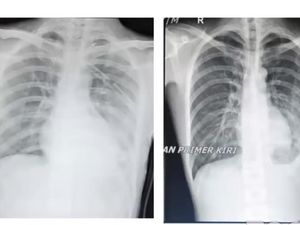

Menyoal Pneumotoraks, Kondisi di Balik Paru-paru Pria Pecandu Vape 'Bolong'

Pemuda asal AS yang baru berusia 19 tahun mengalami paru-paru 'berlubang' akibat kecanduan vape. Menurut diagnosis, ia mengidap pneumotoraks spontan. Apa itu?